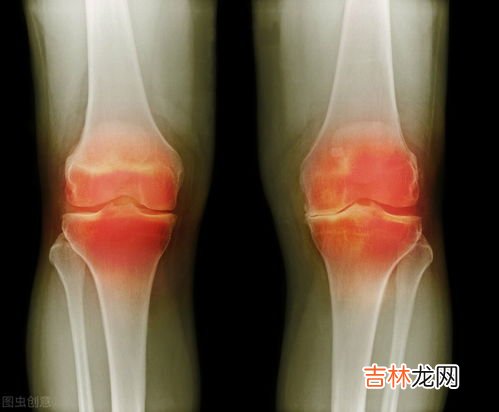

2、关节宝有什么功效使用关节宝最为显著的一个功效就是它能够帮助大家缓解关节疼痛 , 经常做运动的人关节难免会出现磨损的情况,在磨损的情况出现之后,疼痛感也难免会出现 。大家感到关节疼痛的时候一定要使用关节宝来缓解疼痛,让自己可以正常的走路 。而对于更多的人来说,身体会因为早年间没有能很好的调养自己的身体,导致关节出现了炎症,特别是风湿这种疾病在出现之后,一到阴雨天,大家就十分的难受,不但不能够正常的工作,连休息的时间都感到相当的不适,而使用关节宝则能够帮助大家治疗关节风湿的情况 。目前大家对于关节宝有什么功效都非常的了解了,觉得自己有需要就要前去购买它了 。

5、立新世纪关节宝功效【关节宝有什么功效,腰椎间盘突出吃法-国关节宝有什么功效呢】立新世纪关节宝这款保健产品,针对于常见的关节疼痛以及关节酸痛,还有关节炎以及风湿性关节炎等问题,都有着很好的改善作用 。不仅如此,立新世纪关节宝对于腰椎间盘突出和骨质增生,以及经常出现的颈椎疾病和腰酸腿疼的问题,也是效果显着的 。该产品不仅可以改善一些关节常见的问题,还可以起到很好保护关节的作用 。